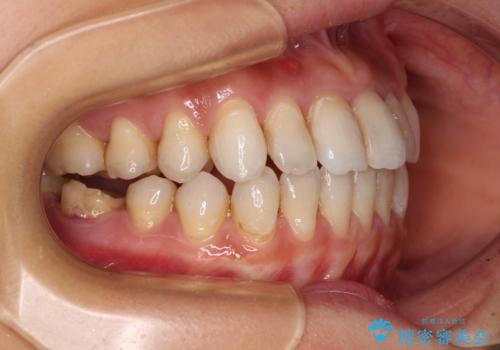

- 上下前歯の開咬とデコボコを気にして来院された患者様です。

開咬(オープンバイト)はインビザラインによる矯正治療がワイヤー装置と比べて圧倒的に有利であるため、インビザラインによる矯正治療を行うこととしました。

通院されなかった時期があって治療期間が長くなったり、奥歯に抜歯が必要な歯があったりと、治療は一筋縄にはいきませんでしたが、何とか治療を終えることができました。

今後はインプラント治療やむし歯治療を進めて行く予定です。